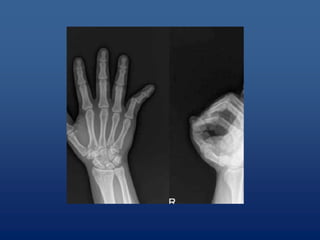

• Identifying fractures (cracks) and breaks or

infections in bones and teeth1

Uses of x-rays •Identifying fractures (cracks) and breaks or infections in bones and teeth1 • Diagnosing cavities and evaluating structures in the mouth and jaw • Picking up on signs of joint changes that indicate arthritis using a special type of X- ray image called an arthrogram • Revealing tumors on bones •